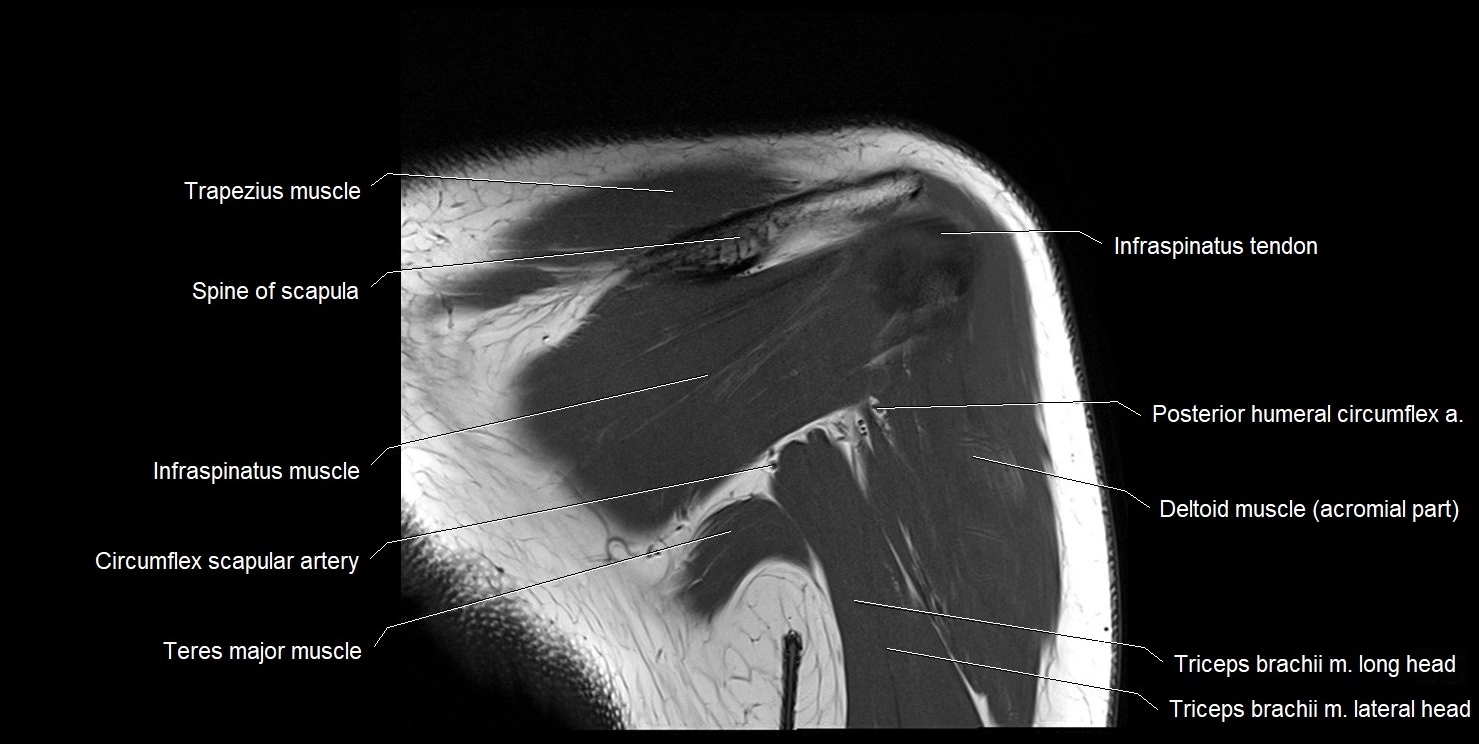

CT image

image